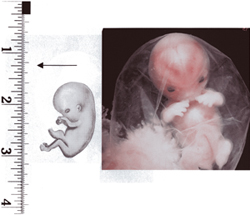

anne karnında bebek fotoları

4 haftalık bebek görüntüsü 25 haftalık bebek 25 görüntüsü

anne karnında 4 haftalık

anne karnında 4 haftalık